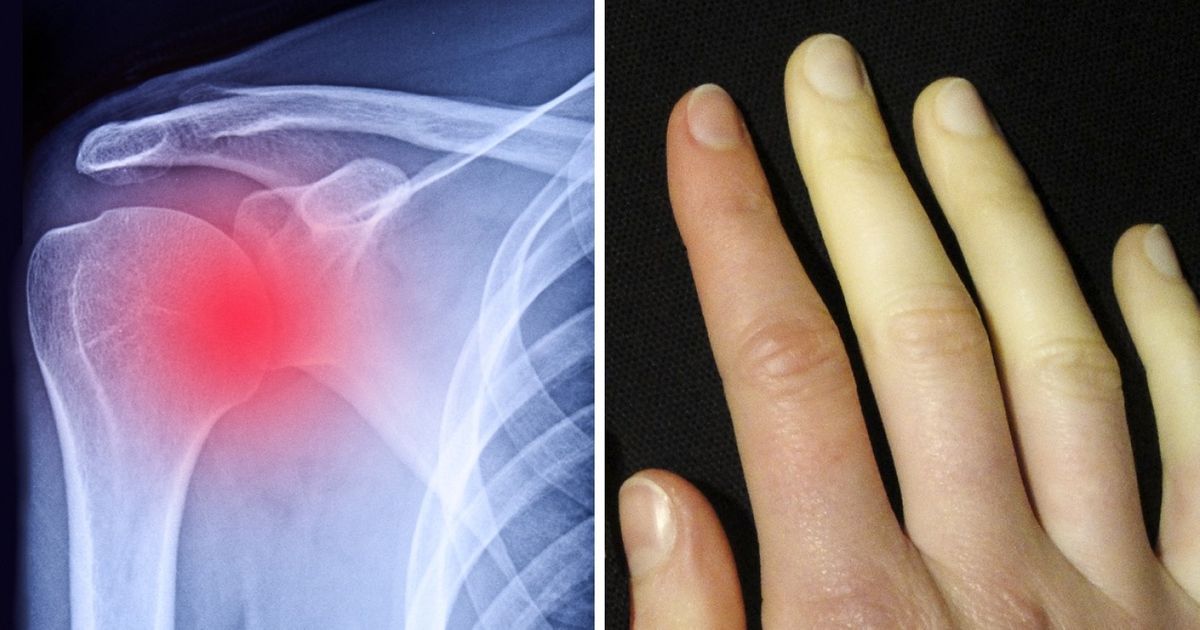

If you’ve noticed that your fingers often change color, you should be aware that there is a serious reason for this. This is a sign that you have Reynaud’s Syndrome — a condition where low temperatures cause spasms in the blood vessels, leading to changes in the color of the skin on your fingers.

Some people’s shoulder joints appear to be loose or can be moved in an unusual number of directions. This is an indication of an unstable shoulder joint — a condition where the ball of the shoulder bone comes out of the socket of the joint. It may be the case that these individuals were simply born with very flexible ligaments, or it could have been caused by a sports injury. In both cases, however, this is a dangerous condition that can lead to injuries and dislocation.